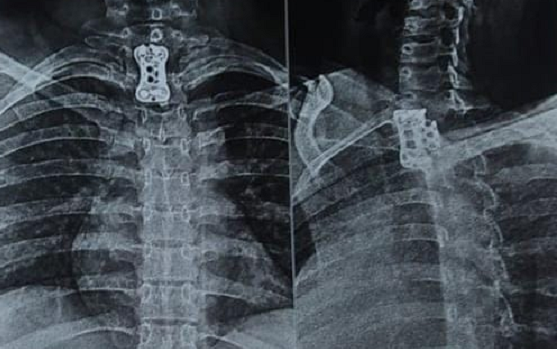

Dr. Somashekar D is an experienced spine surgeon in Bangalore. He is currently practising as a Consultant - Spine Surgery at Manipal Hospital Jayanagar, Bangalore. With nearly 10+ years of expertise in spine care, Dr. Somashekar has established himself as a highly skilled spine surgeon, contributing to over 1,500+ spine surgeries independently, ranging from simple decompressions to complex spinal reconstructions. His practice is deeply rooted in precision-based techniques and evidence-guided clinical protocols, ensuring both safety and long-term functional outcomes for his patients. He is a top spine surgeon in Jayanagar.

We offer comprehensive treatment for spine issues that is on par with any leading spine center worldwide. Our services encompass both non-surgical and surgical treatments tailored to address your specific condition. Our expertise covers a wide range of spine surgeries, including minimally invasive spine surgery, cervical spine surgery, scoliosis surgery, and complex spine surgeries.

• Spine trauma

Covers a wide range of spine surgeries, including complex spine surgeries.